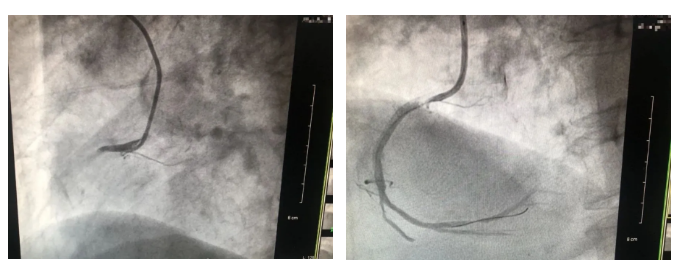

与此同时,医院手术室一切准备就绪。由于超高龄心肌梗死患者往往基础毛病多,血管病变严重且复杂,介入治疗难度大、风险高,急诊冠脉介入治疗通过不开刀、介入微创的手段,能尽早开通梗塞的心脏血管,挽救濒死心肌。在取得家属同意后,救治团队随即紧急开展手术。

当天夜里23时,手术顺利完成。以“门球时间”计算,即急性心梗患者从急诊室至首次球囊扩张的时间,也是影响患者抢救成功率的重要因素,用时仅54分钟。随后,阿公被送至监护室进一步观察。期间,医护团队及时救治、精心护理,阿公各项指标均逐步平稳恢复,三天后转到普通病房,并于近日康复出院,家属方连着向医院表达感谢。